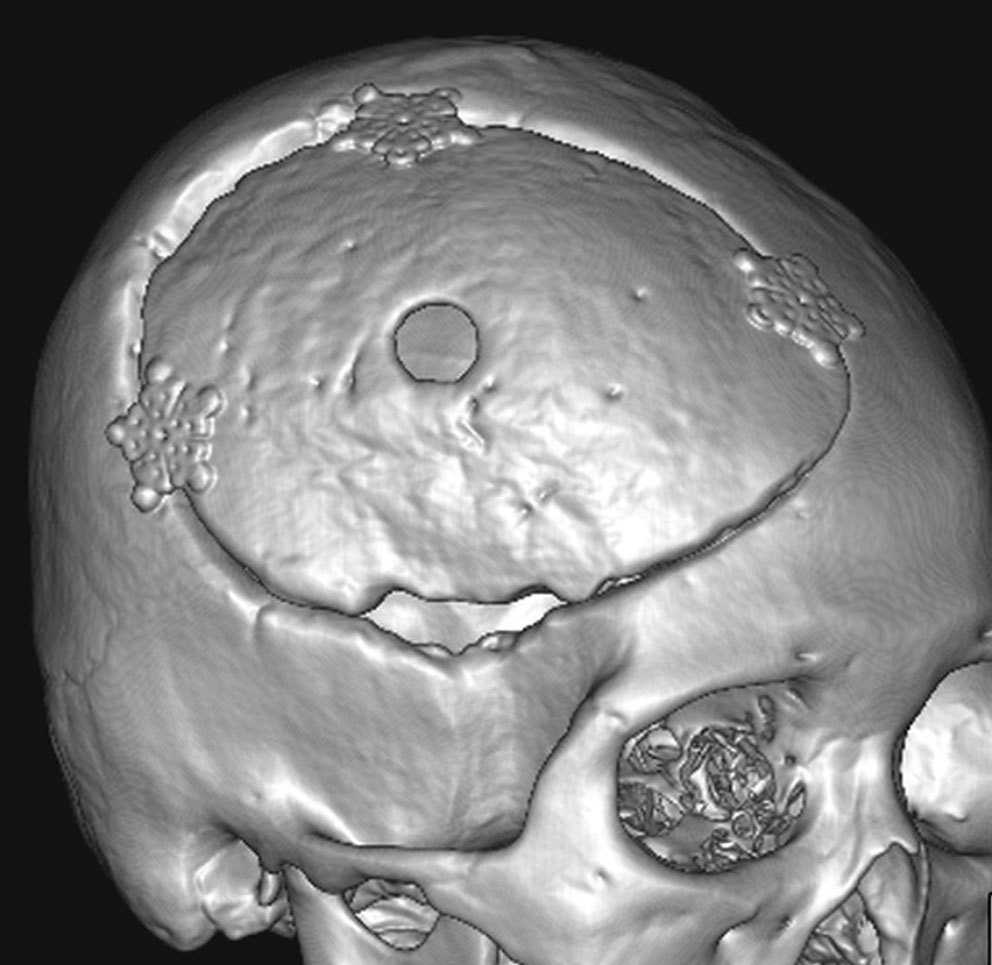

骨内髄膜腫 osseous meningioma

骨内増殖をする髄膜腫です。頭蓋骨腫瘍と間違えるようなものです。触った感じは骨腫ですが,CTでは,表面が毛羽立っていて,頭蓋冠に浸潤していることが特徴です。浅側頭動脈からの豊富な血流があります。

わずかですが頭蓋内にも腫瘍があり,硬膜が肥厚してガドリニウム増強されます。

頭蓋骨をかなり広範におかすので骨は捨てません。開頭して取り外した骨の厚くなっている部分と髄膜腫で軟らかくなっている部分を削除して,それから骨片をオートクレーブで短時間熱処理して,元あった所にもどします。下の画像は手術後1年半が経過したものですが,髄膜腫の再発はなく,熱処理骨弁は吸収されないで生着しています。